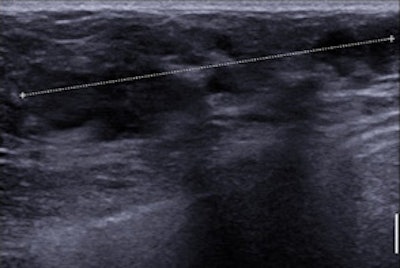

A 34-year-old woman with 50-mm suspicious palpable lump in the left breast. Top: Mammogram (lateromedial view, spot compression). It shows no mass, no architectural distortion, just three microcalcifications. Bottom: Sonogram shows no mass but a focal heterogeneity ("nonmass"). BI-RADS 4. Biopsy under ultrasound guidance: grade III ductal invasive carcinoma HER2+. All images courtesy of Dr. Martine Boisserie-Lacroix.